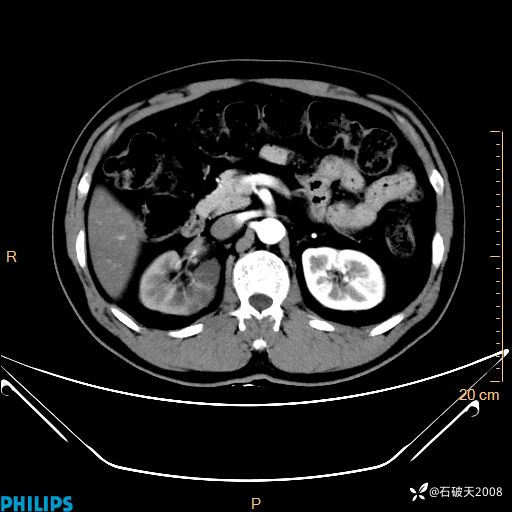

增强轴位